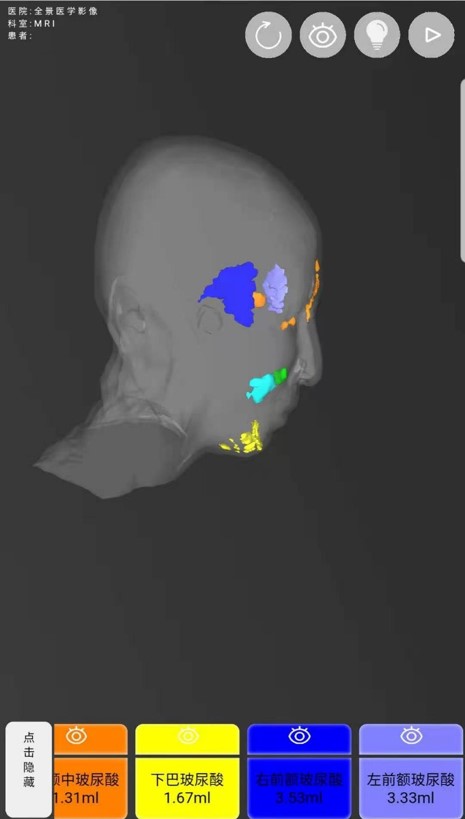

病史:患者女性,26岁,面部玻尿酸填充后,为保证长期的美观性,需了解填充物的分布情况,是否需要再次注射,2020年3月20日来我中心行MRI玻尿酸植入物评估影像检查。双侧额部、面颊部、鼻翼两侧、鼻根部及上颌部皮下见片状异常信号影,T1WI呈稍低信号、T2WI呈高信号。

MR三维重建对于面部填充剂患者能够清晰显示填充剂范围及部位,残留多少及体内形态,可判断填充剂在面部的变化。

填充物-原始分布体积(毫升): |

18.28 |

左侧面部最大厚度(毫米) |

11.4 |

右侧面部最大厚度(毫米) |

10.7 |

下巴部位最大厚度(毫米) |

14.3 |